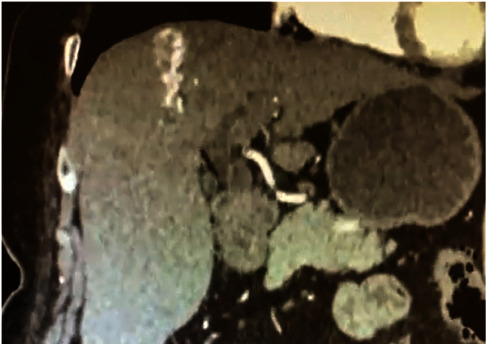

Hereditary hemorrhagic telangiectasia (HHT), also known as Rendu-Osler-Weber syndrome, is a vascular disorder of autosomal dominant etiology. The hallmark clinical feature is the presence of recurrent episodes of epistaxis in patients with vascular malformations and a tendency to bleed. We present the case of a 71-year-old woman who presented to the emergency department with upper gastrointestinal bleeding caused by esophageal varices, in conjunction with gastric angiodysplasias. The presence of oronasopharyngeal telangiectasias and hepatomegaly raised suspicion of HHT. The diagnostic workup confirmed the presence of angiodysplasia in the gastric region, portal arteriovenous malformation, and a pulmonary shunt.

遗传性出血性毛细血管扩张症(HHT)又称伦杜-奥斯勒-韦伯综合征,是一种常染色体显性遗传的血管疾病。其主要临床特征是患者反复发作鼻衄,伴有血管畸形和出血倾向。本病例是一名 71 岁的妇女,因食管静脉曲张并发胃血管增生症引起上消化道出血而到急诊科就诊。口咽部毛细血管扩张和肝脏肿大使她怀疑自己患有 HHT。诊断检查证实了胃区血管增生、门静脉畸形和肺分流。